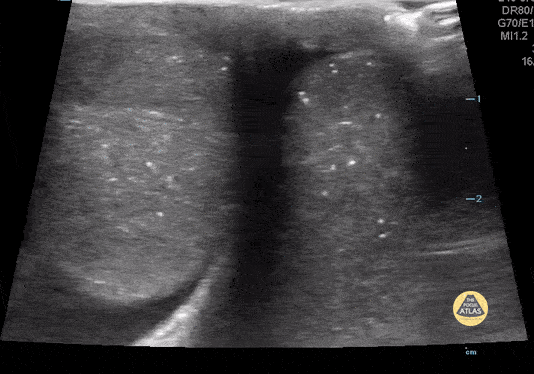

14 yo male presents with right testicular pain. POCUS shows high riding testicle with absent flow in buddy view as well as isolated view. Image one is the isolated view. Image 2 depicts buddy view. Case Series 2 of 2